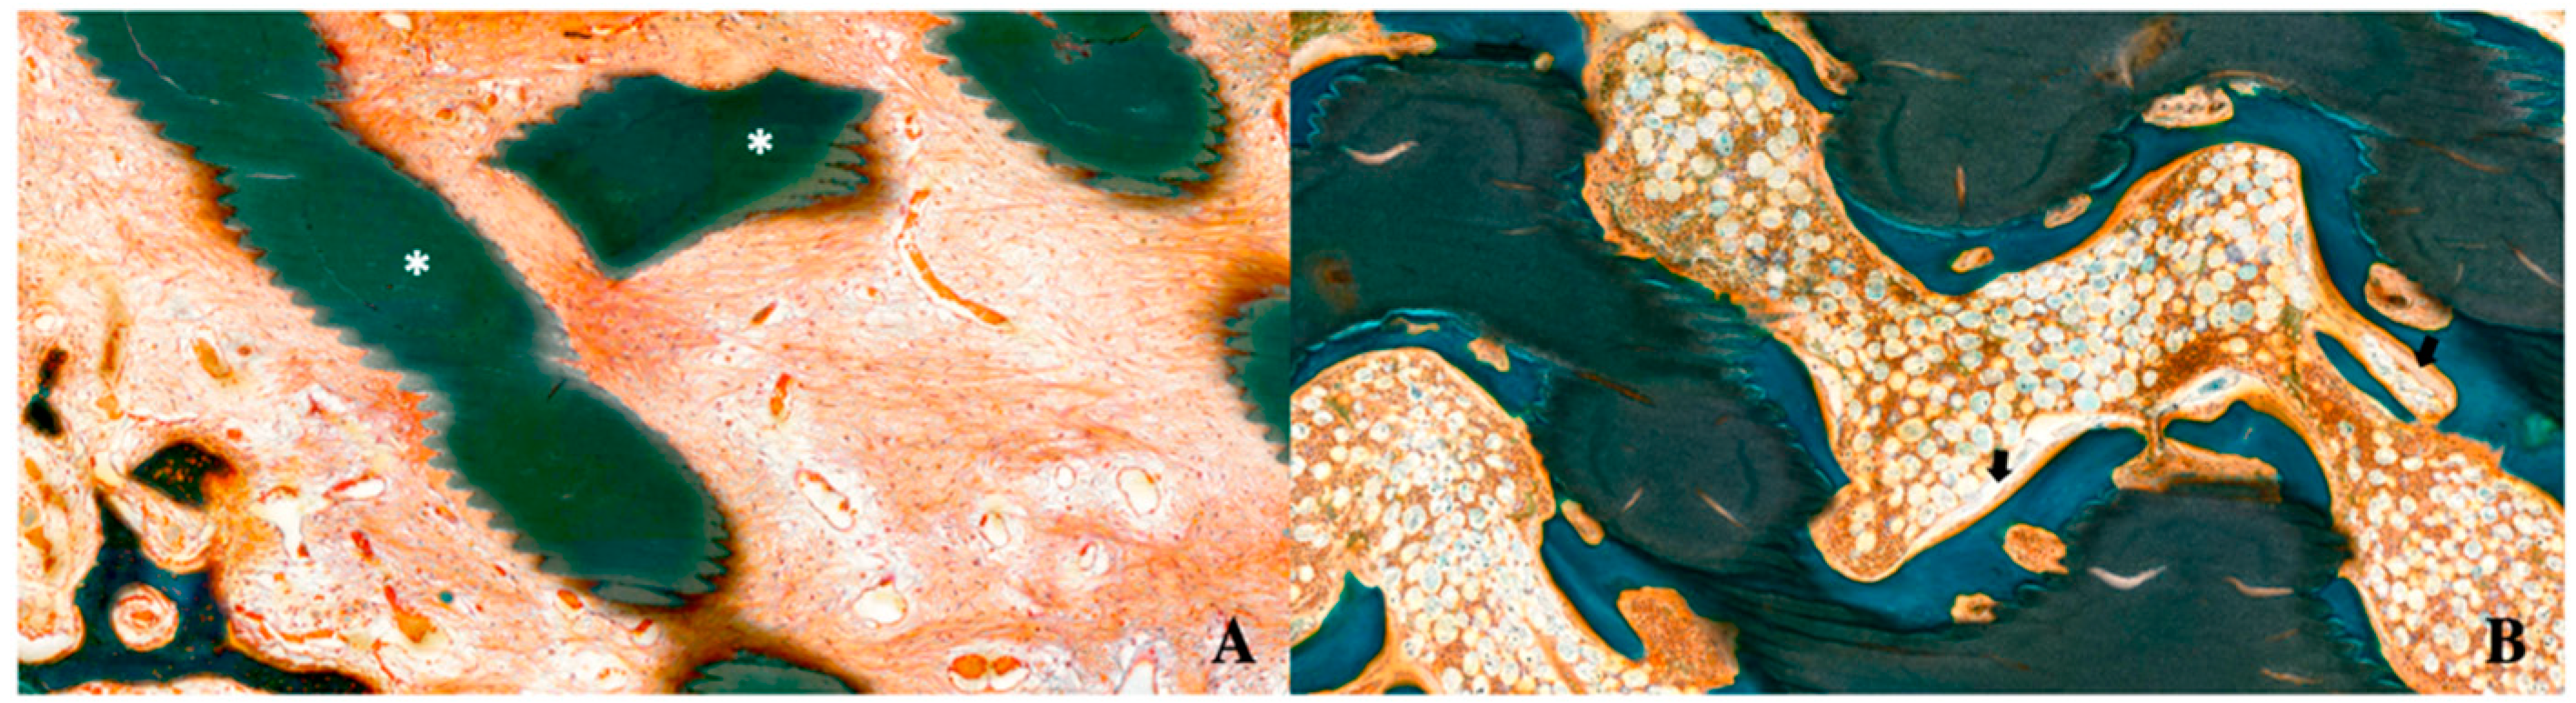

7.5. Histomorphometric Evaluation